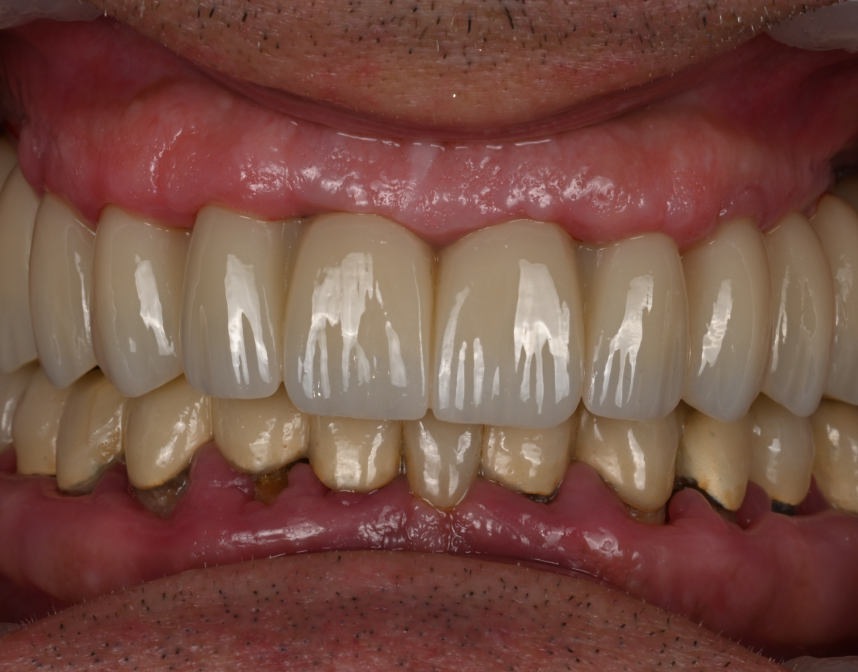

Cas cliniques

La réhabilitation globale est une solution complète pour ceux qui ont des problèmes de santé bucco-dentaire multiples et complexes. Elle consiste en un plan de traitement personnalisé, conçu pour traiter toutes les affections dentaires en une seule fois. Cette approche globale permet de restaurer l’harmonie du sourire, tout en améliorant la santé bucco-dentaire de façon durable.

Au cabinet dentaire du Docteur Malthieu, nous croyons fermement que la réhabilitation globale est souvent la meilleure voie à suivre pour nos patients. Elle offre des avantages indéniables, notamment une efficacité de traitement accrue et des résultats durables. La réhabilitation globale peut traiter simultanément plusieurs problèmes, ce qui minimise le nombre de visites nécessaires et réduit les délais de guérison.